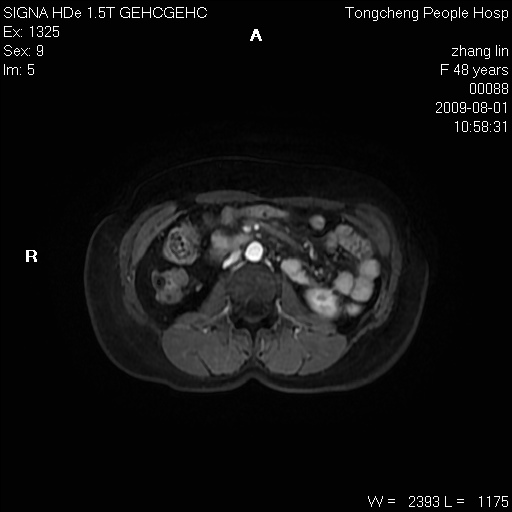

女,48岁。健康体检,彩超发现右肾占位性病变。平素健康。

临床诊断:右肾占位性病变,性质待定(囊肿?肿瘤?)。

上中腹部mr平扫+增强扫描,图像如下:

右肾上极见一类圆形病灶,t1wi呈等信号t2wi呈等高混杂信号,三期增强无强化,边界清---考虑囊肿出血。

同反相位均表现为等信号,病变无强化,考虑含蛋白的囊肿可能,弥散加权相或许有些帮助,

肝囊肿

慢性胆囊炎